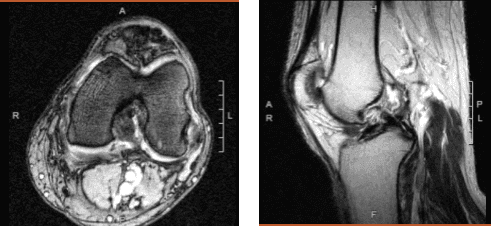

Magnetic resonance imaging of the left knee

The patient is a 60-year-old guy who has seen a doctor several times for pain on the inner side of his left knee, as well as buckling and giving way. We performed an MRI, which revealed a medial meniscus rupture as well as a partial high-grade ACL tear.